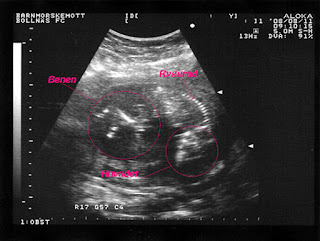

Fostret: Små ljusa hårstrån sk. lanugohår täcker kroppen och till och med undersidan av fötterna. Det fina fjunet kan finnas kvar på vissa delar av kroppen efter födseln, t.ex på ovansidan av öronen. Ögonbrynen och ögonfransarna börjar markeras och på barnets fingertoppar finns helt unika fingeravtryck. Benen har nu kommit ifatt och är i rätt proportion till kroppen. Barnet ser ut som en färdig människa, i miniatyr.